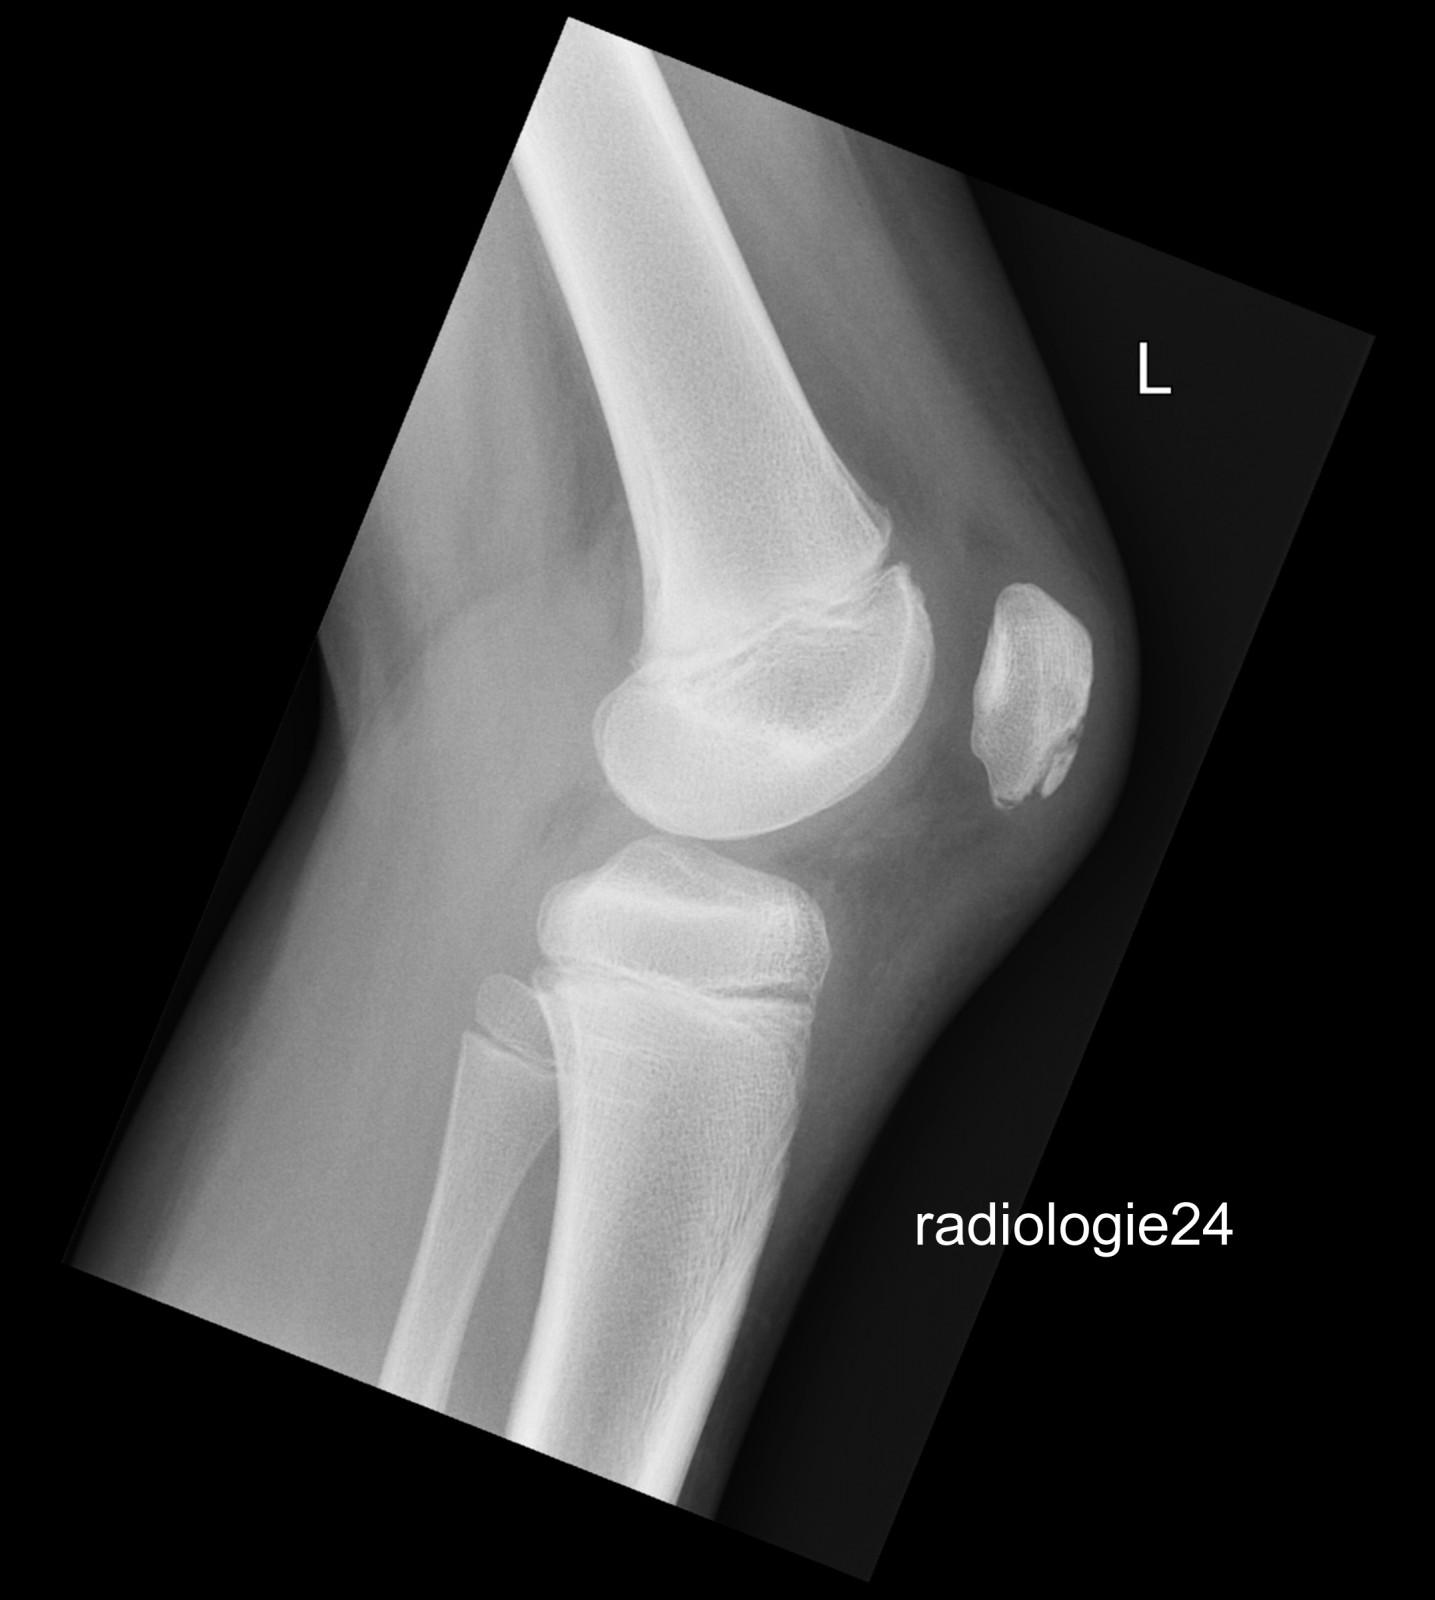

10 jähriger Patient Z.n.Sturz. Schmerzen im Bereich des Kniegelenks Ihre Diagnose?

Bild vergrössern